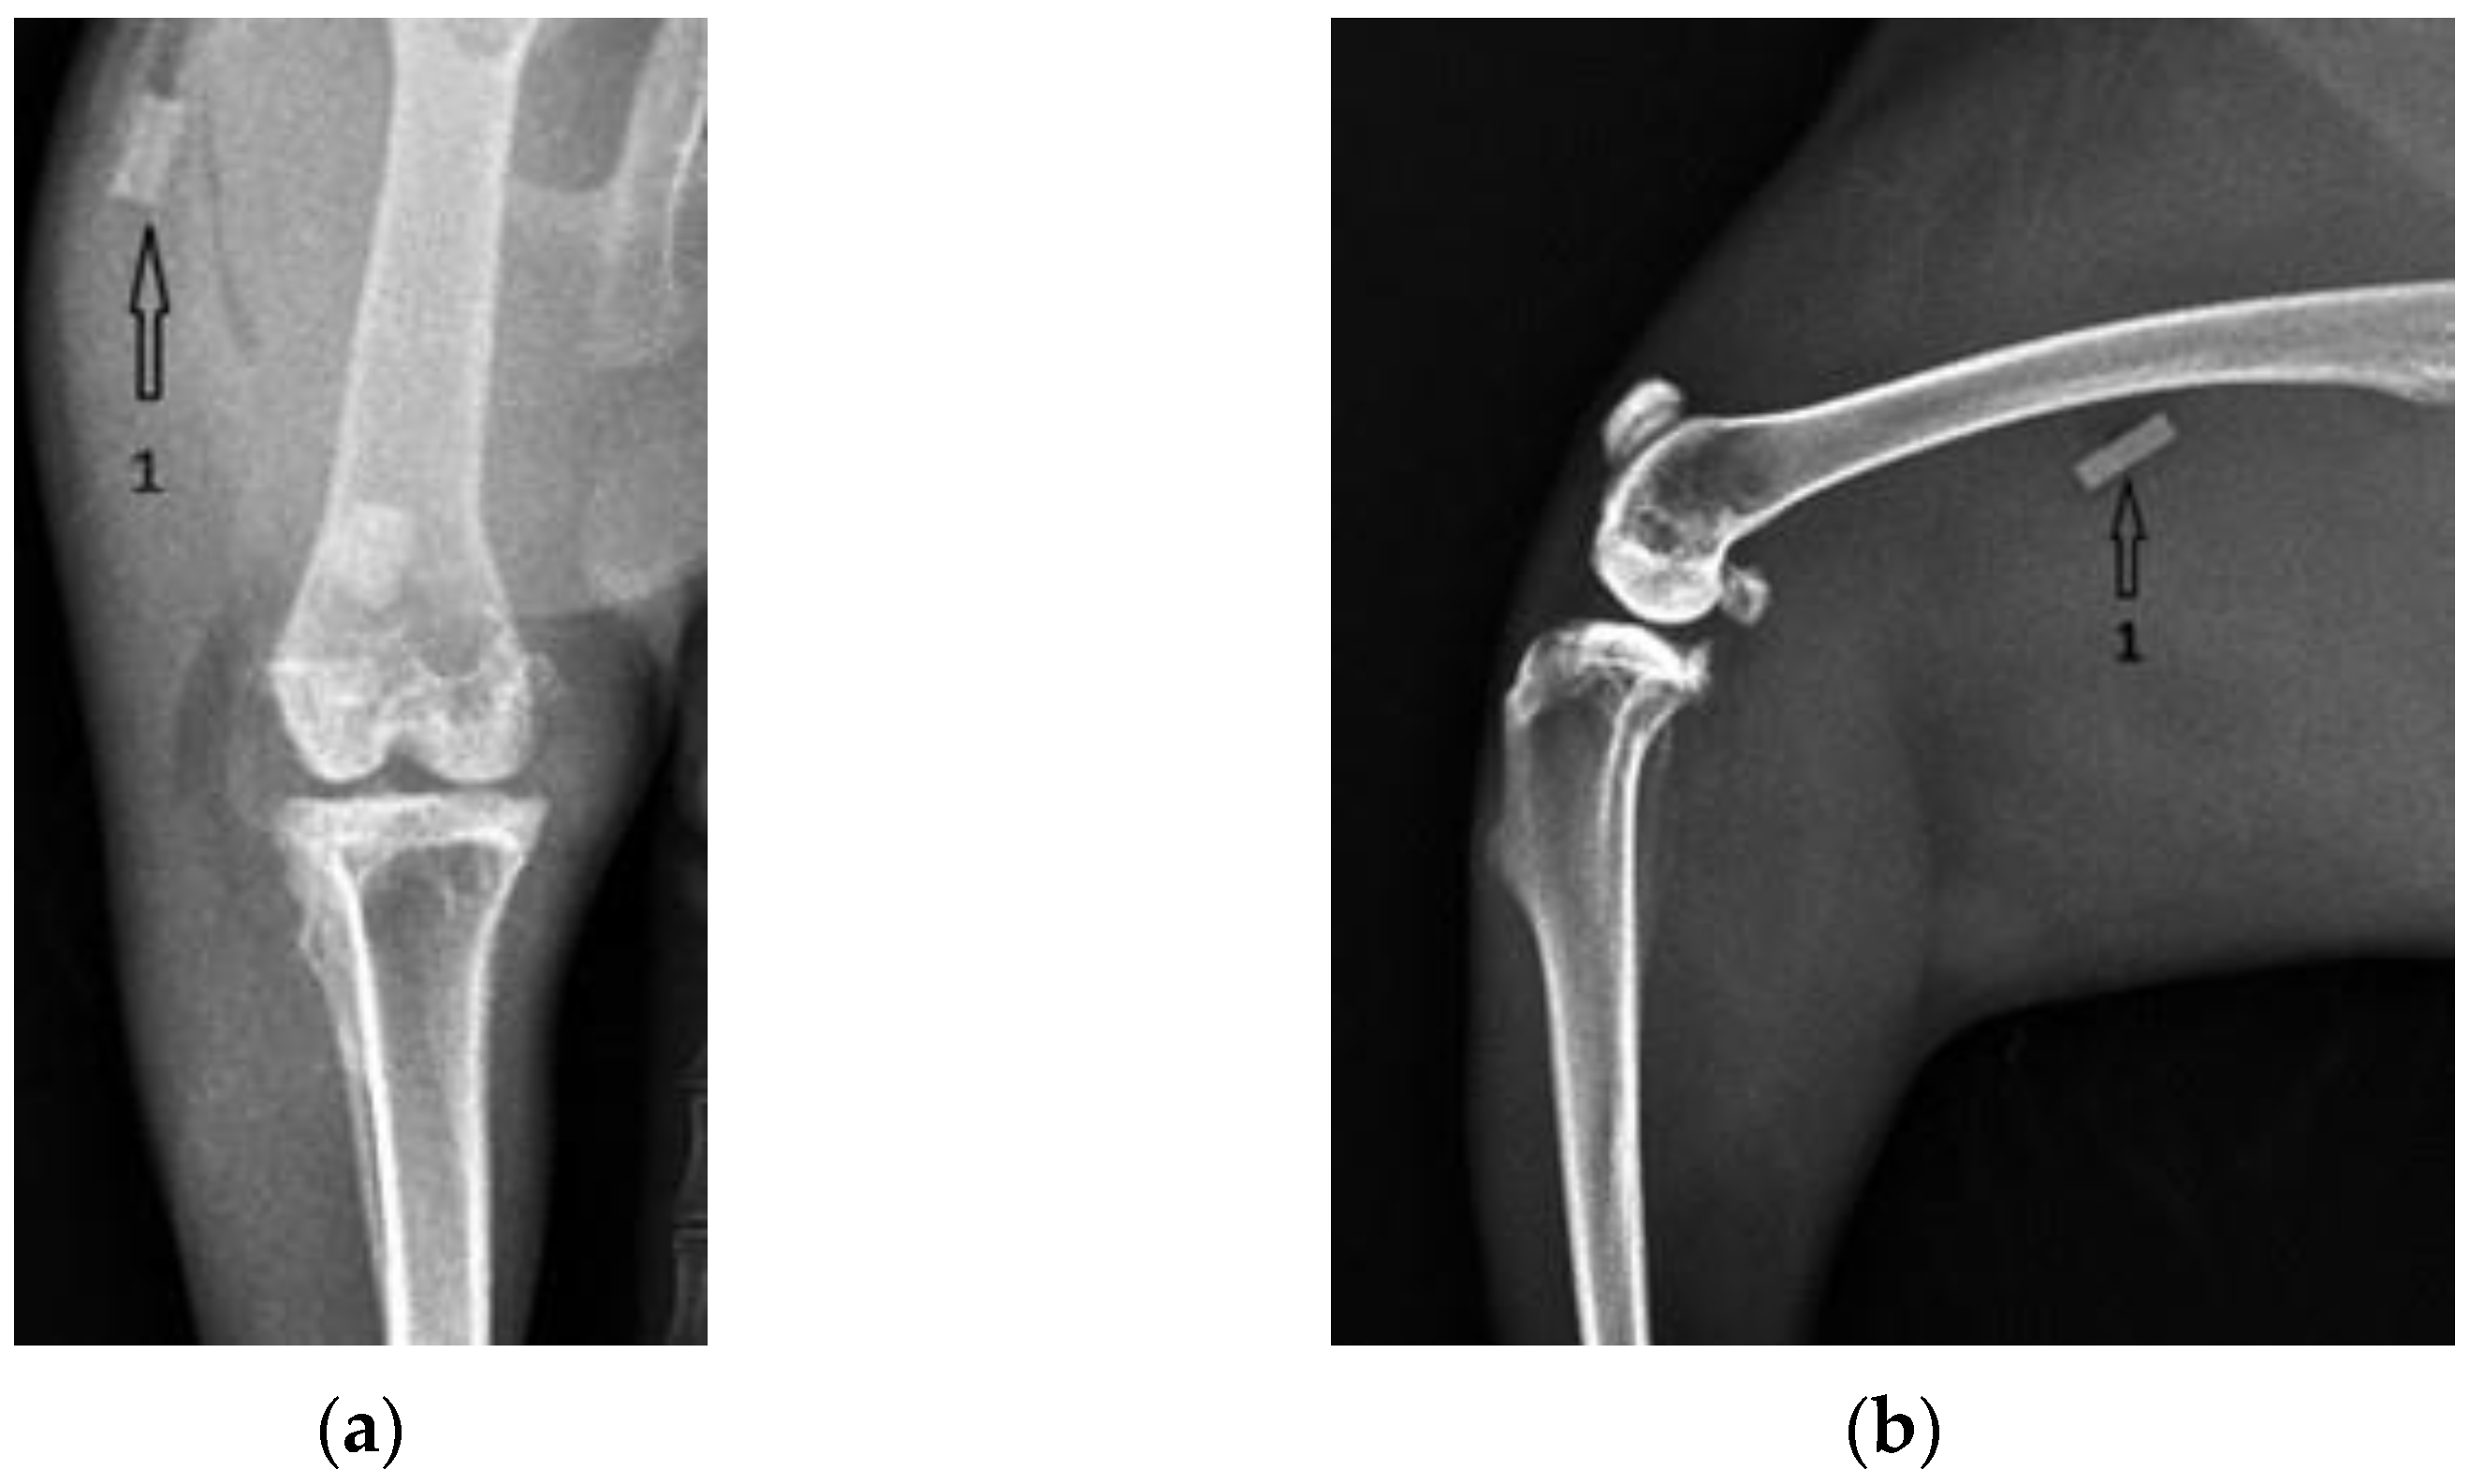

3.1. Radiological Followup